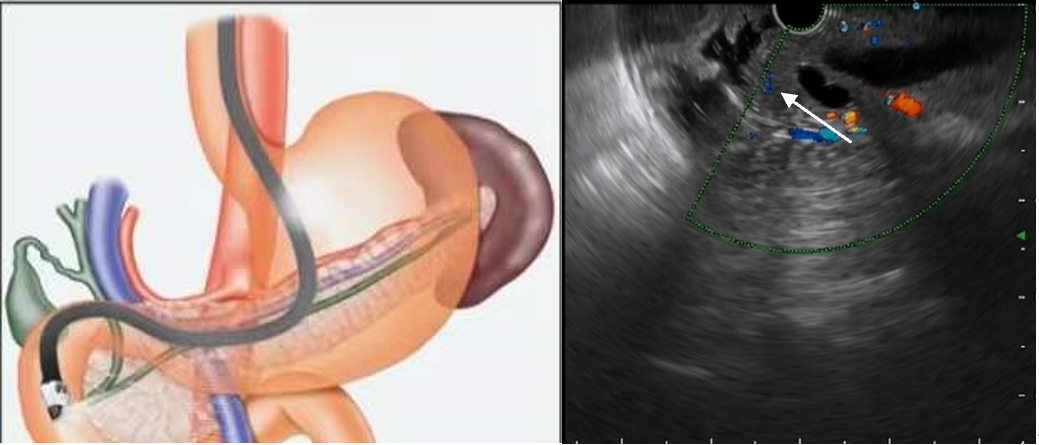

超声内镜探头直接贴近病灶进行超声检查

超声微探头通过钳道对病灶进行超声检查超声内镜的应用1、消化道黏膜下病变的诊断